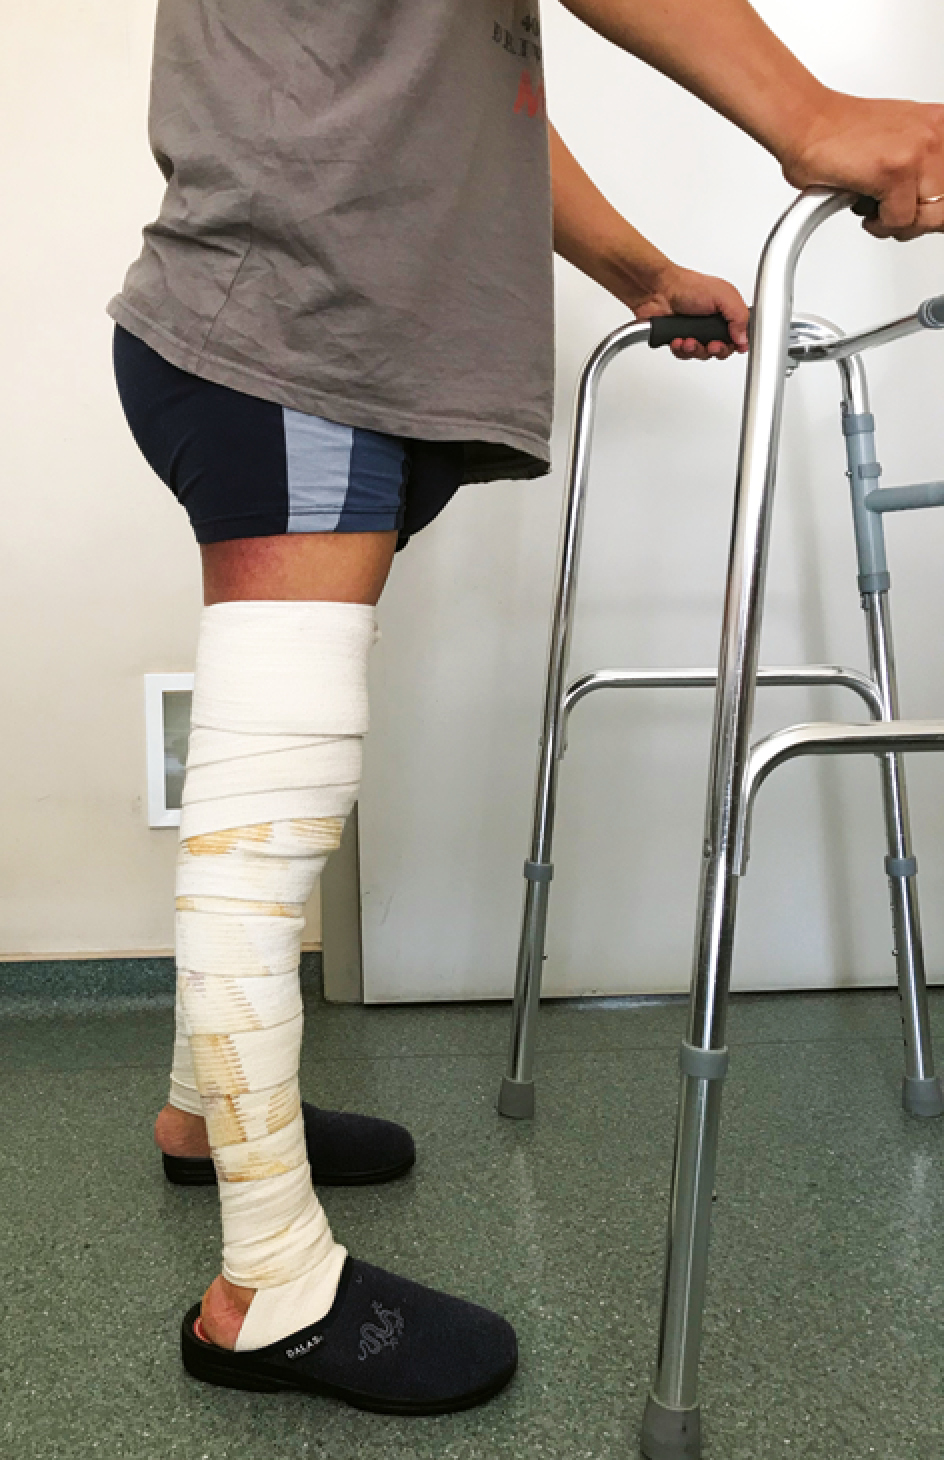

Послеоперационный период. Пациент был активизирован с дополнительной опорой на ходунки с дозированной нагрузкой на оперированную ногу до 25% на 2-е сут. после операции (рис. 6). Осуществлялись регулярные перевязки с оценкой течения раневого процесса, контроль данных лабораторных анализов и коррекция анемии, белкового и электролитного статуса по результатам обследования, стандартная антибактериальная профилактика. Проводилась разработка активных и пассивных движений в прооперированном суставе с применением лечебной физкультуры, аппаратной разработки, применялись физиотерапевтические методы лечения. Послеоперационная рана зажила первичным натяжением. Пациент был выписан на амбулаторный этап лечения в стандартные сроки с рекомендациями по двигательной активности. Через 10 нед. с момента операции пациенту были выполнены контрольные рентгенограммы, оценка объективного и субъективного статуса пациента по результатам первой операции. По данным проведенного обследования рентгенологическая картина соответствовала срокам после операции, объем пассивных движений составлял 15...0...110°, объем активных движений был определен нейромышечным дефицитом. Субъективно пациент положительно оценивал результат операции, отмечал возросшую опороспособность оперированной конечности при сохраняющихся жалобах со стороны правой нижней конечности. В связи с этим было принято решение о проведении второго этапа операции в ближайшие сроки.

Рис. 6. Внешний вид пациента на 3-и сутки после первого этапа операции

Figure 6. The patient’s appearance on the 3rd day after the first stage of the surgery